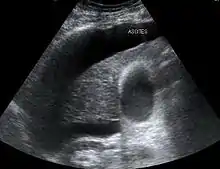

HRS can affect individuals with cirrhosis, severe alcoholic hepatitis, or liver failure, and usually occurs when liver function deteriorates rapidly because of a sudden insult such as an infection, bleeding in the gastrointestinal tract, or overuse of diuretic medications. HRS is a relatively common complication of cirrhosis, occurring in 18% of people within one year of their diagnosis, and in 39% within five years of their diagnosis. Deteriorating liver function is believed to cause changes in the circulation that supplies the intestines, altering blood flow and blood vessel tone in the kidneys. The kidney failure of HRS is a consequence of these changes in blood flow, rather than direct damage to the kidney. The diagnosis of hepatorenal syndrome is based on laboratory tests of individuals susceptible to the condition. Two forms of hepatorenal syndrome have been defined: Type 1 HRS entails a rapidly progressive decline in kidney function, while type 2 HRS is associated with ascites (fluid accumulation in the abdomen) that does not improve with standard diuretic medications.

In contrast, type 2 HRS is slower in onset and progression, and is not associated with an inciting event. It is defined by an increase in serum creatinine level to >133 μmol/L (1.5 mg/dL) or a creatinine clearance of less than 40 mL/min, and a urine sodium < 10 μmol/L.[7] It also carries a poor outlook, with a median survival of approximately six months unless the affected individual undergoes liver transplantation. Type 2 HRS is thought to be part of a spectrum of illness associated with increased pressures in the portal vein circulation, which begins with the development of fluid in the abdomen (ascites). The spectrum continues with diuretic-resistant ascites, where the kidneys are unable to excrete sufficient sodium to clear the fluid even with the use of diuretic medications. Most individuals with type 2 HRS have diuretic-resistant ascites before they develop deterioration in kidney function.[8]

Both types of hepatorenal syndrome share three major components: altered liver function, abnormalities in circulation, and kidney failure. As these phenomena may not necessarily produce symptoms until late in their course, individuals with hepatorenal syndrome are typically diagnosed with the condition on the basis of altered laboratory tests. Most people who develop HRS have cirrhosis, and may have signs and symptoms of the same, which can include jaundice, altered mental status, evidence of decreased nutrition, and the presence of ascites.[2] Specifically, the production of ascites that is resistant to the use of diuretic medications is characteristic of type 2 HRS. Oliguria, which is a decrease in urine volume, may occur as a consequence of kidney failure; however, some individuals with HRS continue to produce a normal amount of urine.[3] As these signs and symptoms may not necessarily occur in HRS, they are not included in the major and minor criteria for making a diagnosis of this condition; instead HRS is diagnosed in an individual at risk for the condition on the basis of the results of laboratory tests, and the exclusion of other causes.[3]